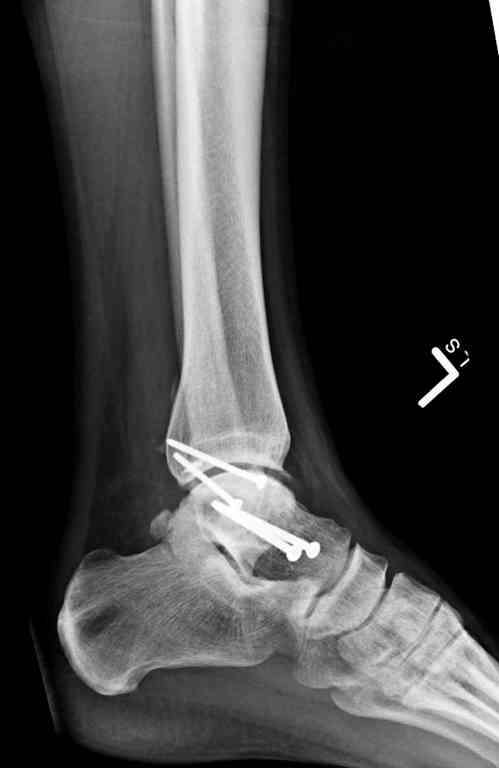

Здесь на фото примеры:

Переломовывих тарана с повреждением медиальной стороны. Через 4 часа после поступления проведена репозиция и фиксация тарана после Irrigation&Debridment. Частичное несращение медиальной лодыжки не беспокоит, вернулся к активному образу жизни. Полная нагрузка разрешена через 11 недель. Финальные снимки через 11 месяцев.